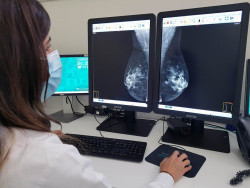

Las estatinas, medicamentos habituales para reducir el colesterol, pueden proteger el corazón de las mujeres del daño causado durante la quimioterapia para el cáncer de mama en etapa inicial, según una nueva investigación publicada en el `Journal of the American Heart Association`, una publicación de acceso abierto de la Asociación Americana del Corazón.

Investigadores de City of Hope, un centro de tratamiento e investigación independiente de renombre mundial para el cáncer, la diabetes y otras enfermedades potencialmente mortales de Estados Unidos, han desarrollado una herramienta que podría predecir si los adultos mayores con cáncer de mama en etapa temprana desarrollarán una reacción grave o mortal a la quimioterapia.